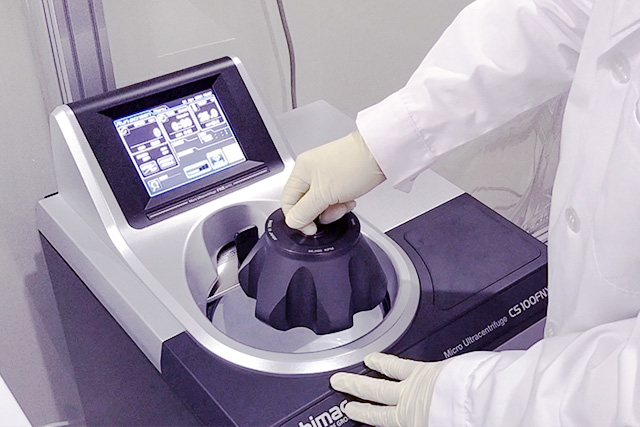

当院では厳密な無菌状態を維持するために特別な「無菌室」を設けています。

- 無菌室内作業風景

当院の無菌室は、細菌やウイルス、微生物からの汚染を防ぐために特別に設計されています。

また、無菌室を有することは、薬剤の品質を維持するため、または免疫抑制を伴うがん患者様にとって重要となります。